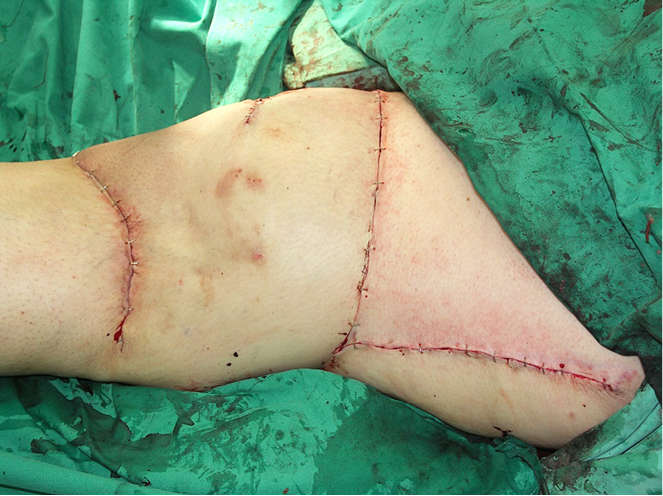

Susiuvus odos kraštus, stebėta gera lopo arterinė perfuzija ir veninis nuotėkis (žr. 4A pav.).

4A pav. Pooperacinis rezultatas transponavus lopą ir susiuvus odą pirmine siūle